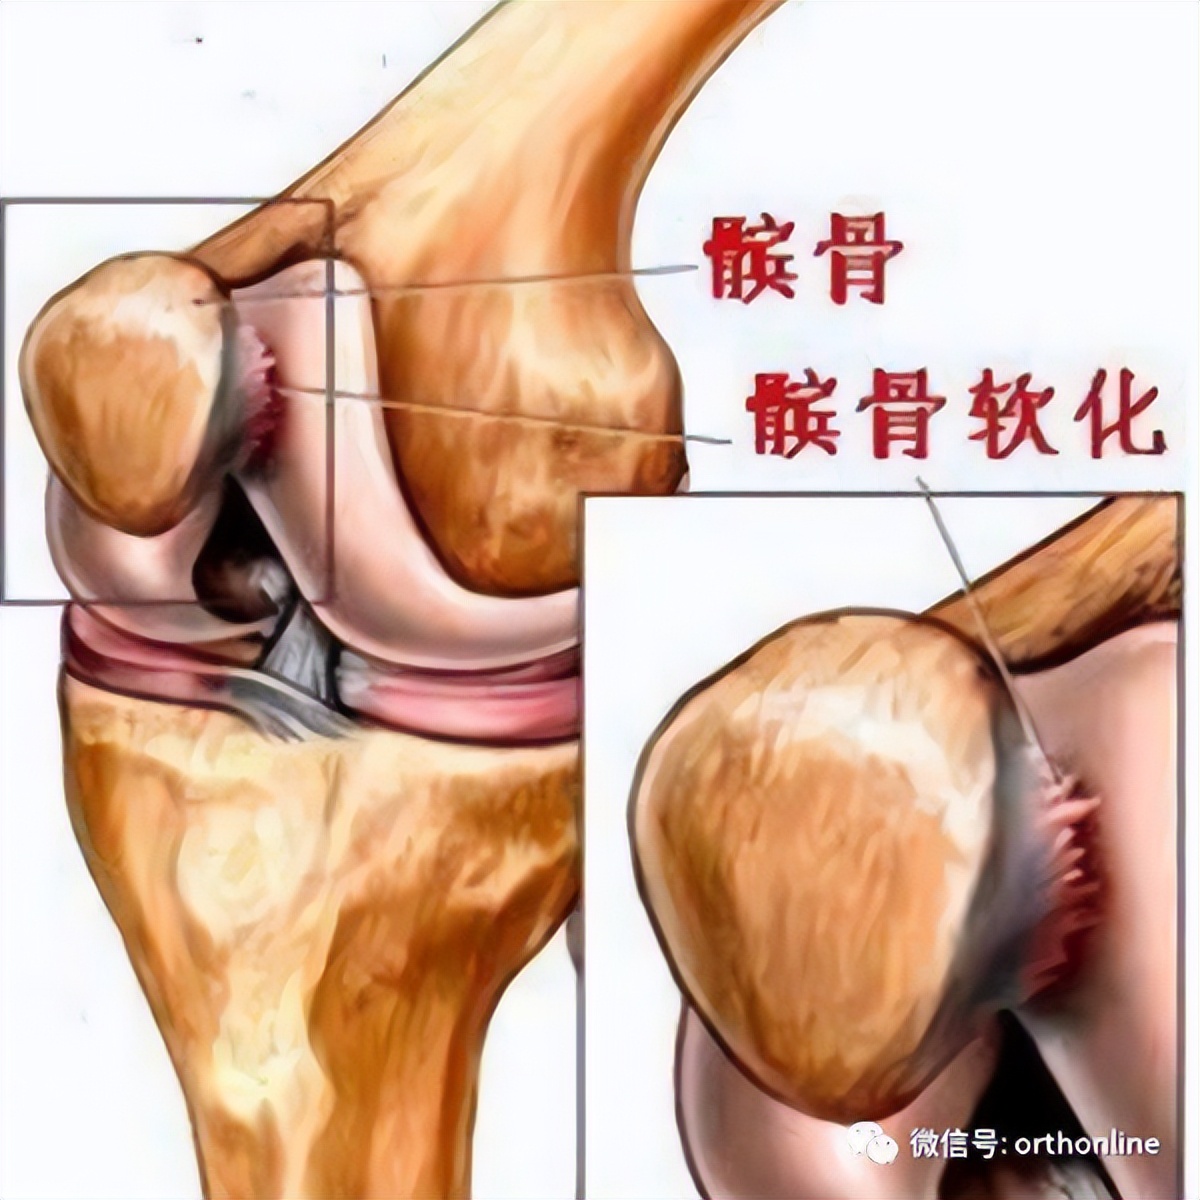

髌骨软化症(chondromalacia Patellae,CMP)又称髌骨软骨炎、髌骨软骨软化症,是一种以膝关节疼痛为主要临床症状的多病因造成的疾病。Budiger 于 1906 年描述了外伤引起关节软骨软化和纤维化;1917年Aleman提出“髌骨软骨软化”病名后一直沿用至今。其主要病理变化是软骨的退行性改变,包括软骨肿胀、碎裂、脱落,最后股骨髁的对应部位也发生同样病变,发展为髌骨关节骨性关节炎。

关节镜下可将髌骨软化分为5级

0级:正常关节软骨

Ⅰ级:关节软骨失去珍珠样外观而变得较暗淡,局部软化,肿胀区或纤毛化区的直径<0.5cm。

Ⅱ级:关节软骨软化区内出现毛刷状或纤毛化改变,深达1-2mm,直径≤1.3cm。

Ⅲ级:软骨的毛刷状或纤毛化改变达关节软骨厚度一半以上,直径>1.3cm,关节软骨表面类似蟹肉样改变,表面有多发软骨碎片附着其下的软骨。

Ⅳ级:关节软骨全层受侵,软骨下骨暴露,表现为进展期髌股关节炎。

Ⅰ~Ⅱ级为早期,主要保守治疗,Ⅲ~Ⅳ级为进展期,需要手术及关节镜治疗。